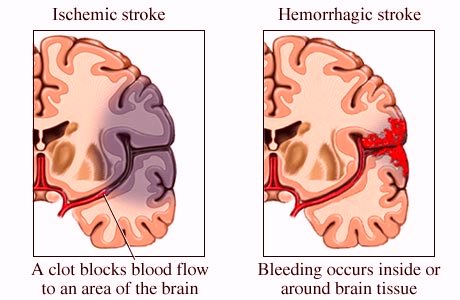

Spontaneous Intracerebral Hemorrhage Pathogenesis Clinical Features Hemorrhage is a medical term that describes any type of bleeding from a damaged blood vessel. it can be minor or severe and external or internal. Hemorrhage is the medical term for bleeding. it most often refers to excessive bleeding. hemorrhagic diseases are caused by bleeding, or they result in bleeding (hemorrhaging). What is a haemorrhagic stroke? haemorrhagic stroke is when you have bleeding in or around the brain. this can damage brain cells. damage to brain cells can affect how the body works. it can also change how you think, communicate and feel. The most serious level of hemorrhage is hemorrhagic shock, a medical emergency that can quickly turn fatal. 2 hemorrhagic shock is when the body loses so much blood that the heart cannot keep up, and vital systems begin failing. Most adults can lose up to 14% of their blood volume without physical symptoms or deviations in vital signs. however, blood pressure drops significantly if a person loses more than 30% of their blood volume. severe hemorrhaging means that a person’s tissue will not supply sufficient oxygen. this can lead to hemorrhagic shock and possibly death. A hemorrhagic stroke occurs when a weakened blood vessel ruptures. it makes up about 13% of all stroke cases. learn the warning signs here.

Hemorrhagic Stroke Intracerebral Hemorrhage Subarachnoid Hemorrhage What is a haemorrhagic stroke? haemorrhagic stroke is when you have bleeding in or around the brain. this can damage brain cells. damage to brain cells can affect how the body works. it can also change how you think, communicate and feel. The most serious level of hemorrhage is hemorrhagic shock, a medical emergency that can quickly turn fatal. 2 hemorrhagic shock is when the body loses so much blood that the heart cannot keep up, and vital systems begin failing. Most adults can lose up to 14% of their blood volume without physical symptoms or deviations in vital signs. however, blood pressure drops significantly if a person loses more than 30% of their blood volume. severe hemorrhaging means that a person’s tissue will not supply sufficient oxygen. this can lead to hemorrhagic shock and possibly death. A hemorrhagic stroke occurs when a weakened blood vessel ruptures. it makes up about 13% of all stroke cases. learn the warning signs here.

Intracerebral Hemorrhage Cause Symptoms And Treatment Most adults can lose up to 14% of their blood volume without physical symptoms or deviations in vital signs. however, blood pressure drops significantly if a person loses more than 30% of their blood volume. severe hemorrhaging means that a person’s tissue will not supply sufficient oxygen. this can lead to hemorrhagic shock and possibly death. A hemorrhagic stroke occurs when a weakened blood vessel ruptures. it makes up about 13% of all stroke cases. learn the warning signs here.